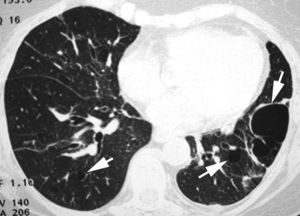

Neumonía intersticial linfocíticaLa NIL es un término clínico-patológico45,46. Histológicamente se caracteriza por una infiltración intersticial difusa por linfocitos policlonales. Suele afectar a mujeres de una edad media de 50años. Los síntomas clínicos son disnea, tos y dolor torácico. La TCAR muestra áreas multifocales de densidad en «vidrio deslustrado», generalmente bilaterales y predominantemente localizadas en los lóbulos inferiores, pequeños nódulos centrolobulillares de contornos mal definidos y quistes pulmonares de paredes finas (fig. 10).

Enfermedades del tejido conectivoLa mayor parte de las enfermedades del tejido conectivo pueden afectar al parénquima pulmonar produciendo una neumopatía intersticial, indistinguible de cualquiera de los patrones TCAR descritos en las NII. La presencia de lesiones relacionadas con la conectivopatía de base, como erosiones articulares, dilatación esofágica o aumento de calibre de la arteria pulmonar, es de ayuda en la orientación diagnóstica de las lesiones pulmonares. Sin embargo, en algunos casos la enfermedad pulmonar puede preceder a la aparición de los síntomas clínicos. A pesar de haberse descrito alteraciones pulmonares en casos de lupus eritematoso sistémico, síndrome de Sjögren, enfermedad mixta del tejido conectivo, dermatomiositis o polimiositis y espondilitis anquilopoyética, las 2conectivopatías más frecuentemente asociadas a EPI son la esclerodermia y la artritis reumatoide. Los patrones TCAR más frecuentes en estos pacientes son NINE y la NIU, comunes en la esclerodermia y en la artritis reumatoide (fig. 11)20,47,48. La neumonía organizada se presenta también con frecuencia en las enfermedades del tejido conectivo, generalmente asociada a otros patrones de neumonía intersticial49. El síndrome de Sjögren puede asociarse a diferentes patrones radiológicos, con mayor frecuencia el de NINE y el de NIL, y también a afectación de pequeña vía aérea50. El patrón de NIA puede observarse en la dermatopolimiositis16.